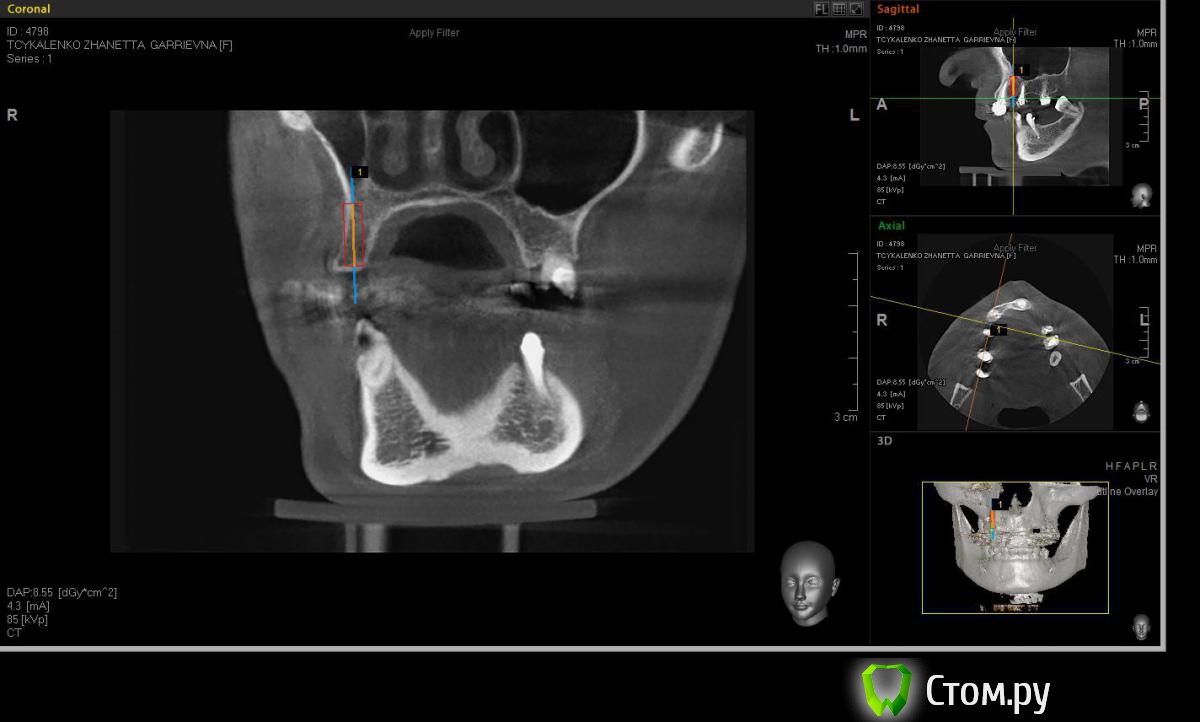

Евгений Ходыкин Опубликовано 20 мая, 2014 Автор Поделиться Опубликовано 20 мая, 2014 Замерил... Ссылка на комментарий

АнтонТЛТ Опубликовано 20 мая, 2014 Поделиться Опубликовано 20 мая, 2014 А теперь замерьте угол в районе 15 зуба через фиссуру Ссылка на комментарий

Евгений Ходыкин Опубликовано 20 мая, 2014 Автор Поделиться Опубликовано 20 мая, 2014 Ну как-то так. Сути не уловил) Свой зуб стоит совсем иначе, да и ширина гребня иная совсем... Ссылка на комментарий

АнтонТЛТ Опубликовано 20 мая, 2014 Поделиться Опубликовано 20 мая, 2014 Суть в том, что изначально не правильно угол замерили 1 Ссылка на комментарий